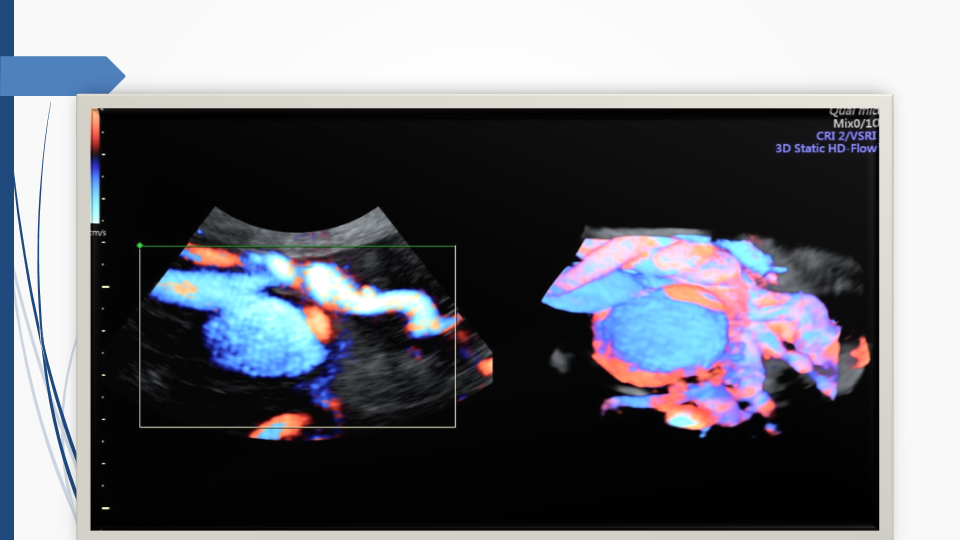

Tầm soát chủ động bất thường dây rốn và tuần hoàn thai để giảm thiểu nguy cơ thai lưu đột ngột - Báo cáo loạt ca hiếm gặp và khuyến nghị thực hành